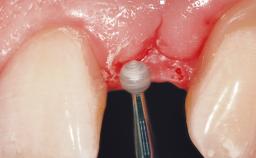

Implant Placement with Simultaneous Contour Augmentation using GBR

Surgical treatment of a 67-year-old male patient exhibiting an extended edentulous space in the anterior maxilla after the removal of three hopeless incisor teeth.

The video demonstrates implant placement using a surgical stent according to the principle of prosthodontically driven implant placement. The deficient ridge is augmented with locally harvested autologous bone chips, a superficial layer of xenogenic DBBM particles and a resorbable collagen membrane. The surgery is completed with a precise, tension-free primary wound closure.

The case concludes with the presentation of the final prosthesis and the esthetic outcome, demonstrating stable soft tissue conditions and stable bone crest levels at the 3-year follow-up.